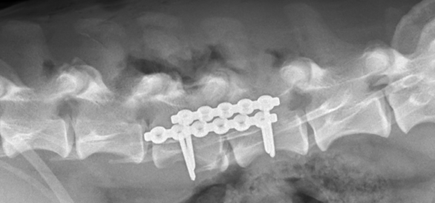

“When Monty came in, he had a number of injuries and was obviously in a lot of discomfort,” said Surgical Clinician, Rhys Treharne. “We did CT and MRI scans to work out what was wrong, and they pinpointed a fracture to his spine and also a tendon rupture to his pelvis.

“If we hadn’t operated the fracture could have got much worse, so we went ahead with surgery and put in plates with screws to repair it. A few days later we carried out another surgery to fix the rupture."